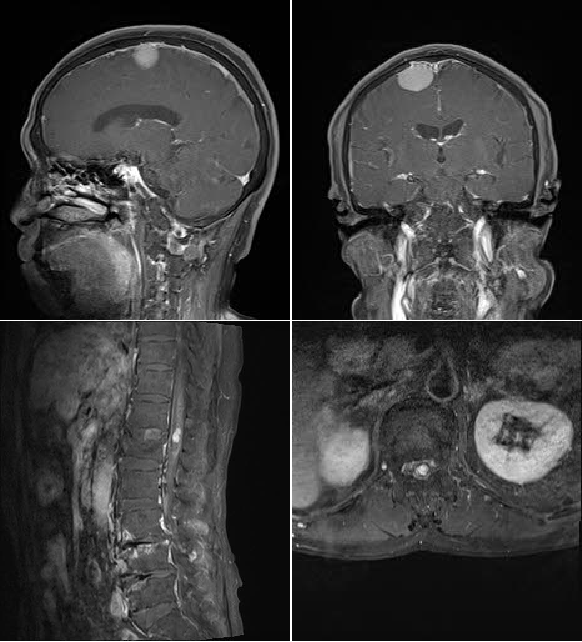

主管医师陆云详细查看患者影像学资料后告知患者,“虽然存在下腰椎严重退变压迫脊髓情况,但腰椎退变性疾病一般不会造成急性脊髓损伤的问题,因此需要进一步完善头颅及全脊柱核磁扫描。”待完善相关影像学检查后,结果提示患者同时存在颅内肿瘤、胸腰段椎管内肿瘤合并下腰椎严重退变性不稳、椎间盘突出等一系列问题。

术前头颅及腰椎MRI